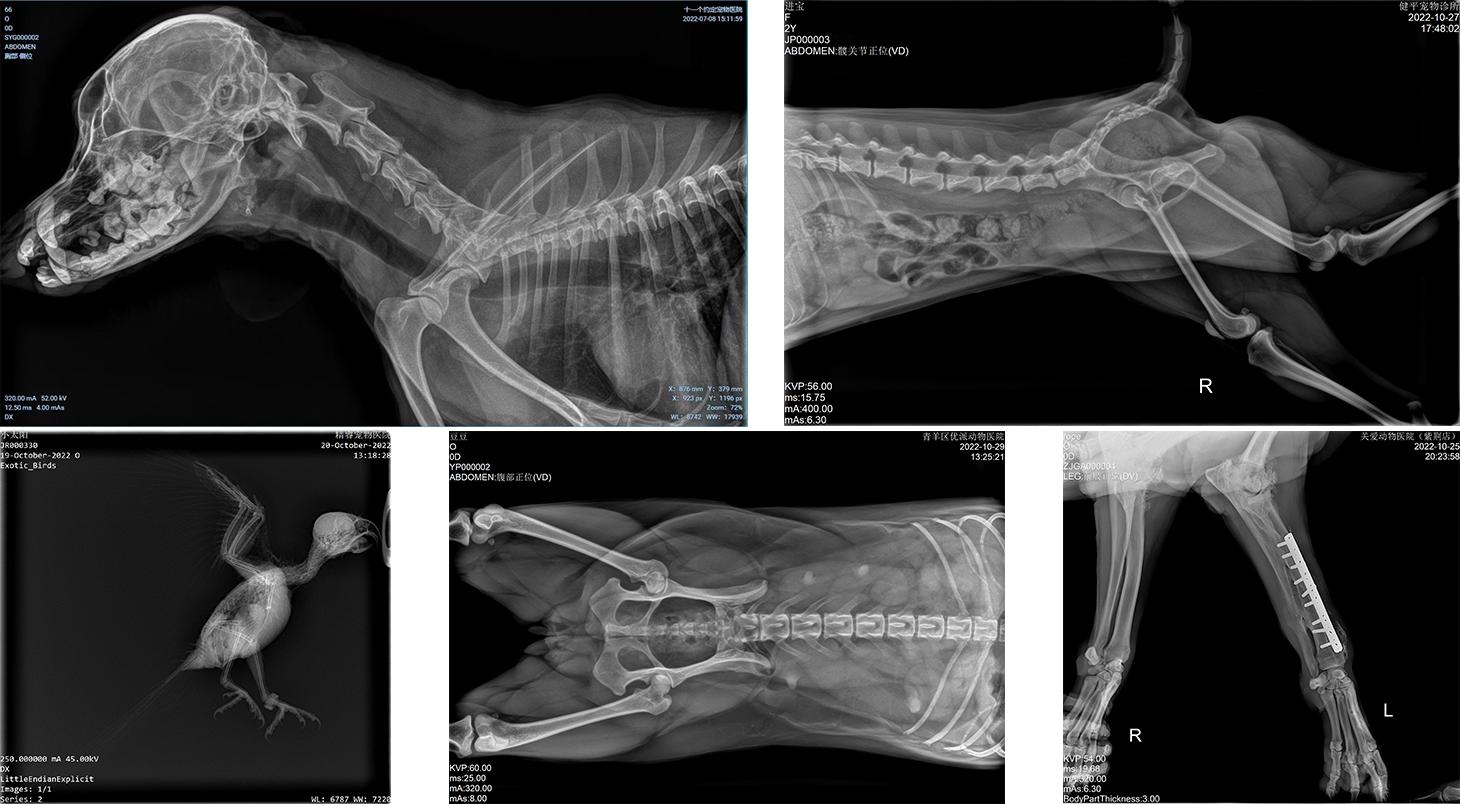

晓智部分临床拍片